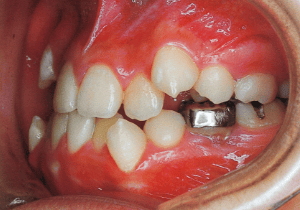

1 At start of treatment 7-21-’88

A case of diverted and cross bite during the deciduous dentition. Despite early treatment, the deviation progressively worsened with age, necessitating surgical treatment. At the initial visit, the patient had a deciduous dentition, and observation was planned (3). With the eruption of the permanent incisors, the mandible shifted slightly to the right, resulting in a cross bite (1) At this point, asymmetry can be confirmed in the front view. However, it is slight. The cephalometric X-ray reveals a structure with a slightly dominant mandible, but asymmetry in the mandibular ramus is not observed.

On the lateral cephalometric radiograph, the vertical height of the face appears greater than its depth. The lower facial height is also high, suggesting a shape somewhat prone to developing a protruding lower bite, though this does not raise significant concern (6). The facial photograph of front view shows slight asymmetry in the face, but it is not particularly extreme (1). The first phase of treatment corrected the anterior cross bite and deviation, but subsequent growth exacerbated the mandibular deviation, necessitating surgical treatment.